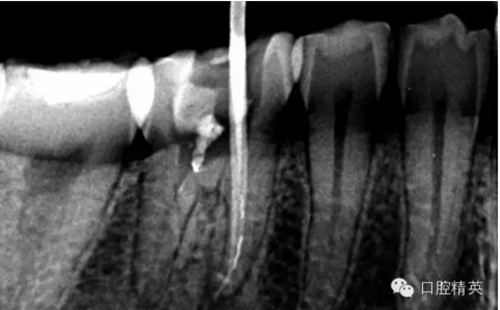

患者,肖某,男,32歲,#36慢性牙髓炎。遠(yuǎn)中舌根根尖1/3彎曲而且鈣化不通,我用盡辦法疏通了很久也沒到達(dá)WL,(我一直在幻想,要是有超聲系統(tǒng)該多好,可是現(xiàn)實(shí)很骨感,我們單位暫時還沒有超聲系統(tǒng)),后來我放棄了,最后的根充片顯示遠(yuǎn)中舌根充填物距根尖端2.84mm,屬于欠填范圍(根管內(nèi)充填物距根尖端2mm以上),其它三根根尖1/3鈣化相對沒那么嚴(yán)重,根充片顯示屬于恰填范圍(根管內(nèi)充填物距根尖端0.5~2mm)。歡迎網(wǎng)友們針對這個病例提出寶貴的建議!

9.png

10.png